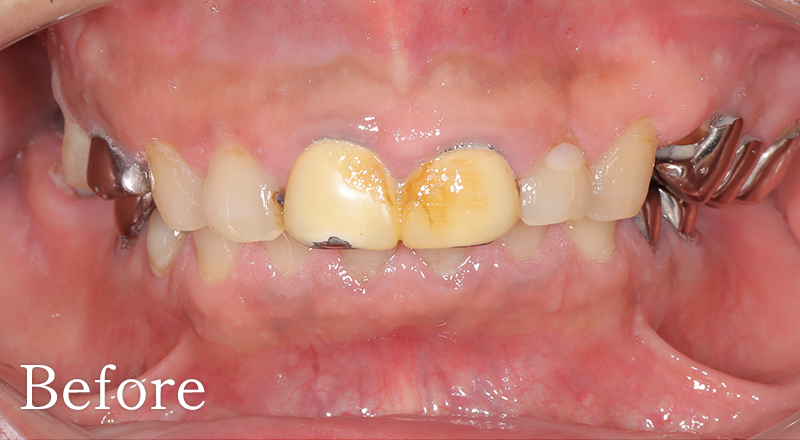

CASE1

右上前歯部にGBRを併用しインプラント治療を行なった1症例

主訴 右上の前歯に歯を入れたい

治療内容 右上側切歯インプラント、GBR

治療期間 約1年

費用 インプラント埋入手術:27.5万円(税込)

セラミック補綴:22万円(税込)

GBR:11万円(税込)